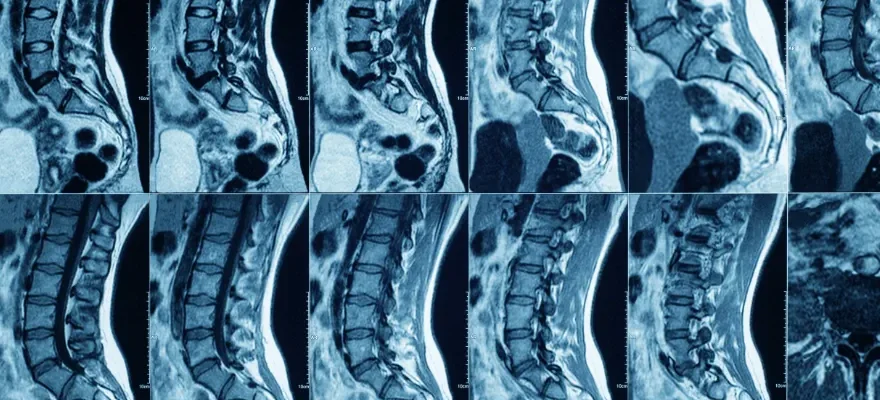

MR Myelografi Nedir?

MR Myelografi, omurilik ve omurilik kanalını çevreleyen zarlar ile omurilik sıvısını detaylı bir şekilde görüntüleyen bir manyetik rezonans (MR) tarama yöntemidir. Geleneksel myelografiye alternatif olarak geliştirilen bu yöntem, kontrast madde kullanmadan veya çok az miktarda kullanarak omurilik ve sinir köklerinin ayrıntılı görüntülerini elde etmeyi sağlar. MR Myelografi, özellikle sinir köklerinin daralması, disk hernisi ve omurilikteki lezyonlar gibi durumların incelenmesinde kullanılır.